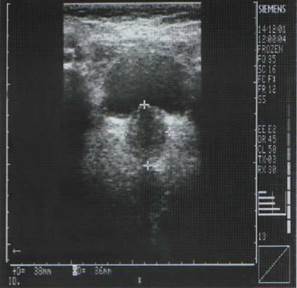

1) Пальцевое ректальное исследование (рис. 1) – базовый метод диагностики опухолей предстательной железы, с его помощью можно выявить наличие опухолевых узлов либо заподозрить новообразование и получить оценочные сведения о сформировавшемся раке предстательной железы. Ультразвуковое исследование (рис. 2) – различные виды ультразвукового исследования предстательной железы дают информацию о наличии опухолевидного образования, его форме, объеме, размере, позволяют выявить изменения в паренхиме предстательной железы, прорастание опухоли в окружающие ткани и органы, позволяют провести сравнительный анализ кровоснабжения участков простаты, используются для контроля проведения биопсии и др. Морфологическое исследование (рис. 3) позволяет поставить окончательный диагноз, определить вид опухоли и ее строение.